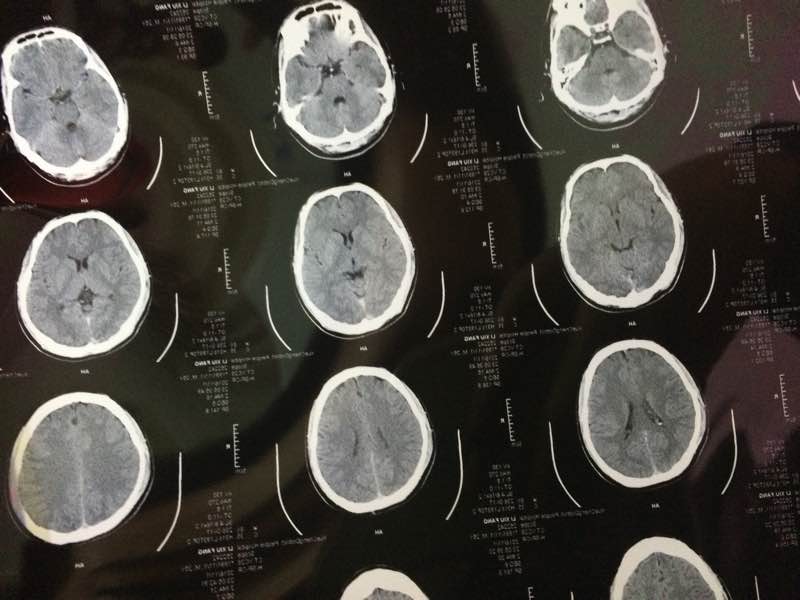

求大神帮忙看看,头还蒙蒙的